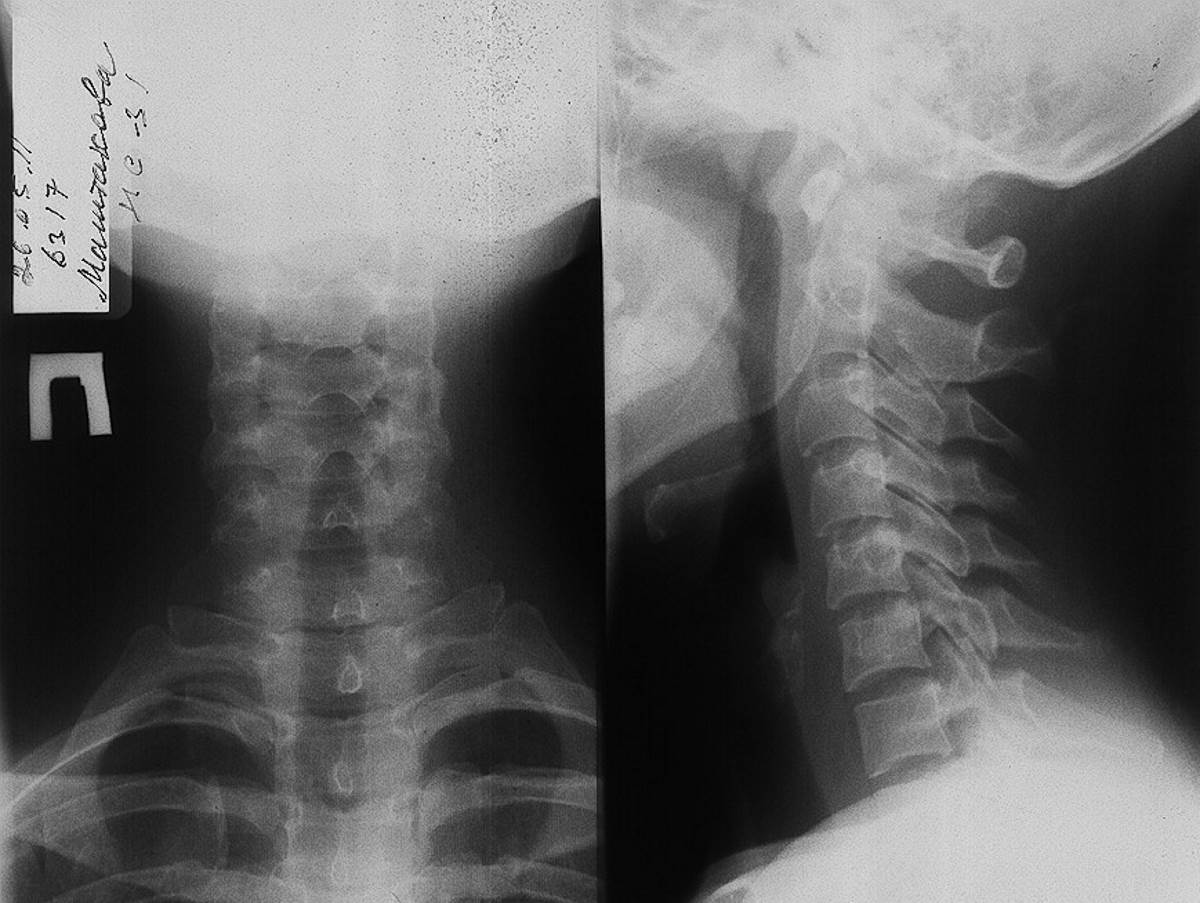

Остеохондроз шейного отдела

Полный размер 1200 × 903 пикселей Как выглядит остеохондроз